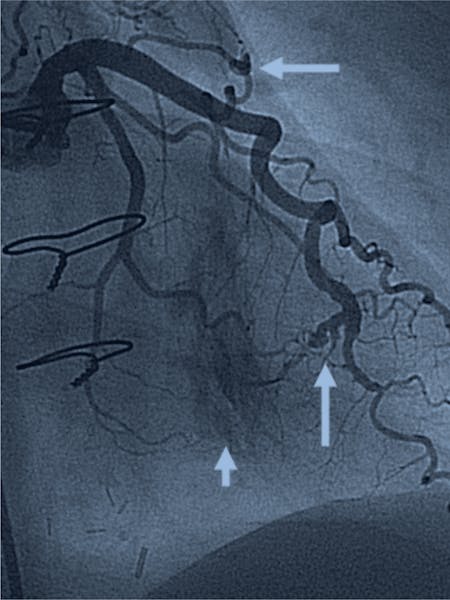

- Angiografia coronariană: considerată standardul de aur pentru diagnosticarea FAVC, această procedură imagistică permite vizualizarea directă a arterelor coronare și a fistulei.